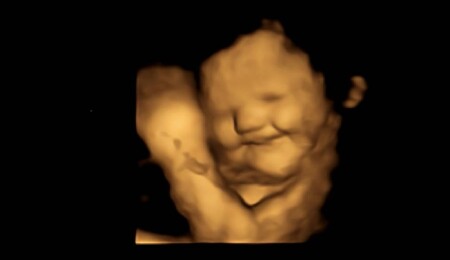

Bulgular fetüslerin, karalahana kapsülü tüketildiğinde yüzünü ekşittiğini gösterdi. Anne havuç tozu aldığında fetüs, karalahana tozu kullanıldığında ya da hiçbir toz alınmadığındaki zamana göre yaklaşık iki kat fazla gülen surat ifadesi takındı.

Bunun ardından fetüslerin, gülme ve ağlamaya benzeyen yüz hareketlerinin analizi gerçekleştirildi.